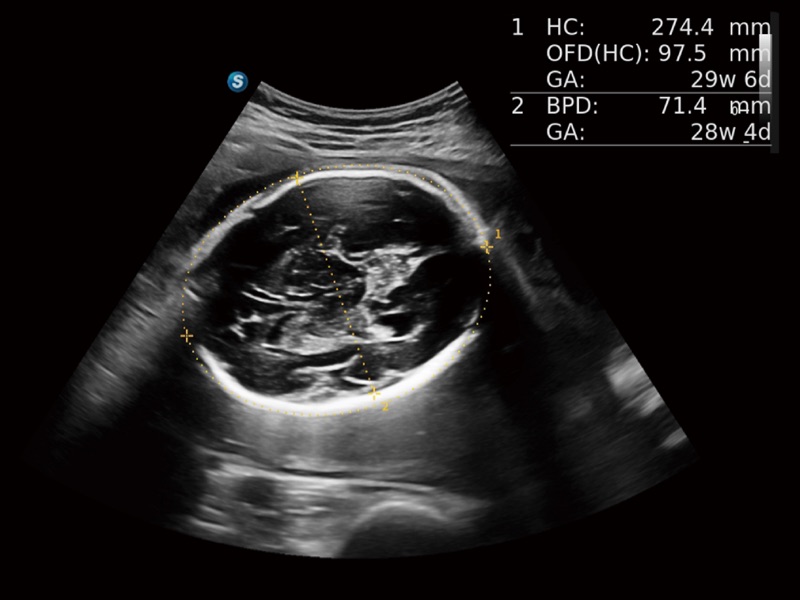

便携式彩色多普勒超声诊断系统

作为开立医疗全新打造的高端全域笔记本超声,X11集成了当前先进的硬件架构和精密的设计工艺,提升多科室临床医生在常规影像检查中的诊断能力,为临床提供全面的诊疗支持。